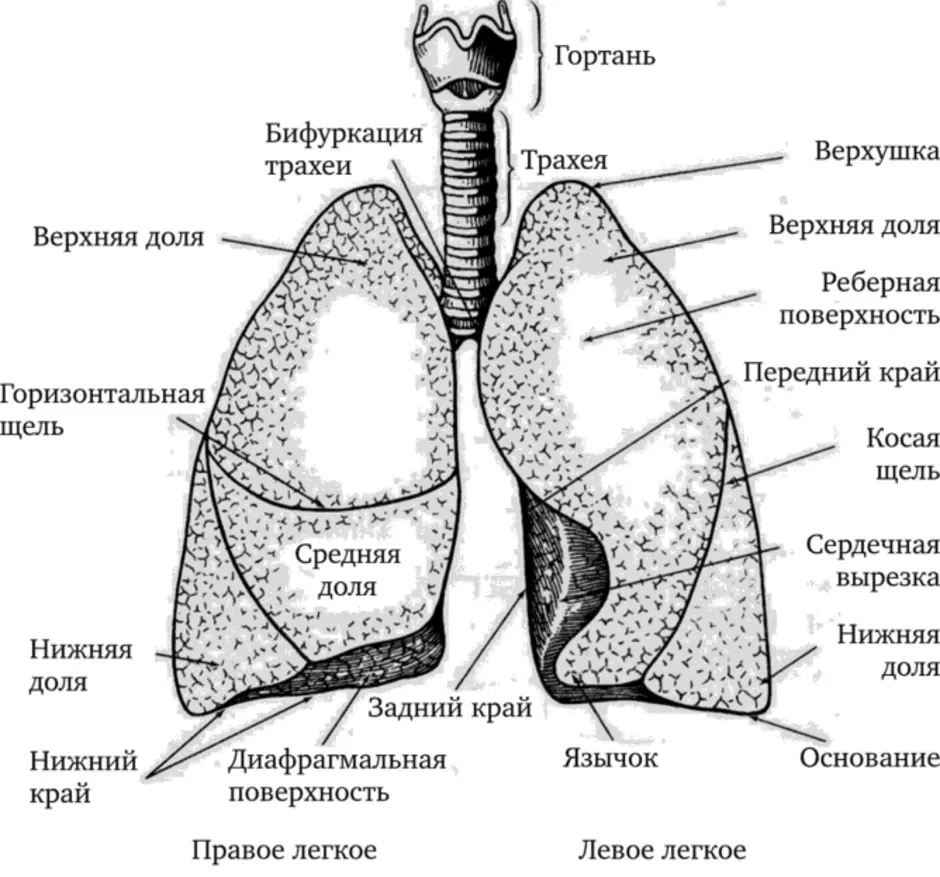

Здоровье дыхательной системы: бронхи и легкие

Раздел: Светлые идеи